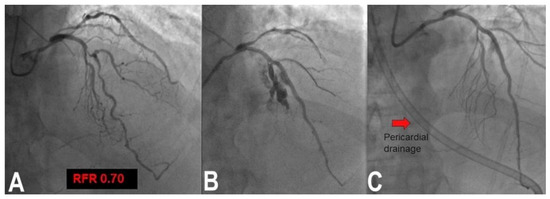

3.6. Perforation/Vessel Rupture